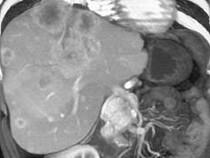

男,48岁,胃癌术后1年,未化疗,CT检查如图所示,最可能诊断为()A.肝癌B.肝转移癌C.肝血管瘤D.肝脓肿E.肝囊肿

问题 男,48岁,胃癌术后1年,未化疗,CT检查如图所示,最可能诊断为()

选项 A.肝癌 B.肝转移癌 C.肝血管瘤 D.肝脓肿 E.肝囊肿

答案 B